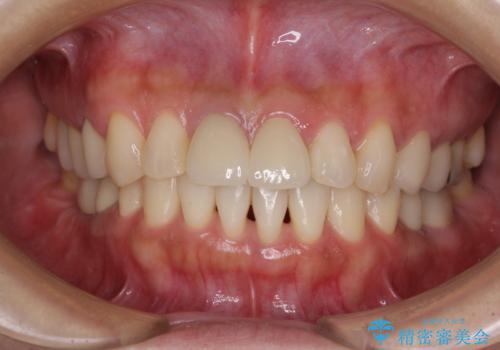

気になる部分を全て治療 総合歯科治療で口腔内環境改善

- 右下の欠損部の治療を希望して来院された患者様です。

部分矯正を行った後にインプラント埋入と手前の歯の根管治療を行い、その後補綴治療を行うこととしました。

治療途中より、上の歯や反対側の銀歯、上顎前歯の色合いや下顎前歯のデコボコが気になってきたため、全てを治療することとしました。

仕事が多忙な方で、来院間隔が開いてしまうことが多く、治療期間はかかりましたが、来院回数は最小限で終えることができました。